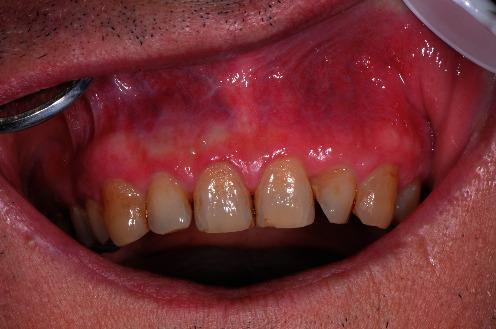

Plasma cell gingivitis (PCG) is a chronic inflammatory disease usually affecting the vestibular portion of the gingival mucosa. Clinical presentation is marked by erythematous macules of intense red color, confluent, and delimited from the healthy neighboring mucosa. Generally asymptomatic, the gum lesions sometimes are accompanied by burning sensations and a sense of local tension. Recommended treatment is the use of topical steroids, but with apparent initial healing that is not stable over time. The present case report concerns a patient diagnosed with PCG in November 2017, with a five-year follow-up. This is the first patient with PCG successfully treated with non-surgical periodontal therapies associated with photobiomodulation (PBM).

A 64-year-old male patient had intense erythema and edema on the vestibular side of the gingival mucosa area from 1.5 to 2.5. The patient's symptomatic subjectivity parameters were evaluated through dedicated questionnaires. Erythema and gingival bleeding were also evaluated. Periodontal charting was not pathological, but intense bleeding was noted. Multiple biopsies were performed, and microscopic findings confirmed the clinical hypothesis of PCG.

The treatment applied was PBM associated with periodontal therapy. The patient demonstrated a progressive improvement in clinical parameters considered and reported symptoms. During the five-year follow-up, no recurrence of the disease was observed.

浆细胞性龈炎(PCG)是一种慢性炎症性疾病,通常累及牙龈黏膜的前庭部分。临床表现为深红色的红斑,融合成片,并与相邻的健康黏膜分界。一般无症状,牙龈病变有时伴有烧灼感和局部紧绷感。推荐的治疗方法是使用局部类固醇,但初期愈合明显但随时间不稳定。本病例报告涉及一名于2017年11月被诊断为PCG的患者,并进行了为期五年的随访。这是首例通过与光生物调节(PBM)相关的非手术牙周治疗成功治疗的PCG患者。

一名64岁男性患者,牙龈黏膜区域1.5至2.5处的前庭侧出现强烈红斑和水肿。通过专门的问卷对患者的症状主观参数进行评估。还评估了红斑和牙龈出血情况。牙周探查无病理性改变,但有明显出血。进行了多次活检,显微镜检查结果证实了PCG的临床诊断。

采用的治疗方法是PBM联合牙周治疗。患者在考虑的临床参数和报告的症状方面有逐步改善。在五年随访期间,未观察到疾病复发。